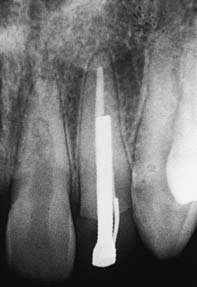

Studies29,31,32 have shown that as post length increases, so does retention. However, the relationship is not necessarily linear (Fig. 12-15). A post that is too short will fail (Fig. 12-16), whereas one that is too long may damage the seal of the root canal fill or risk root perforation if the apical third is curved or tapered (Fig. 12-17). Absolute guidelines for optimal post length are difficult to define. Ideally, the post should be as long as possible without jeopardizing the apical seal or the strength or integrity of the remaining root structure. Most endodontic texts advocate maintaining a 5-mm apical seal. However, if a post is shorter than the coronal height of the clinical crown of the tooth, the prognosis is considered unfavorable, because stress is distributed over a smaller surface area, thereby increasing the probability of radicular fracture. A short root and a tall clinical crown present the clinician with the dilemma of having to compromise the mechanics, the apical seal, or both. Under such circumstances, an apical seal of 3 mm is considered acceptable.